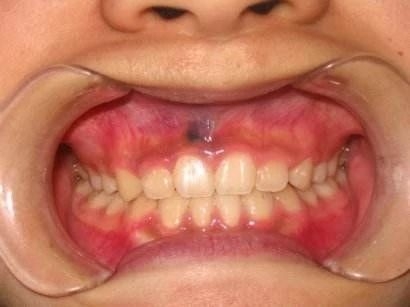

深覆合是一种上下颌牙弓,或上下颌骨垂直向发育异常所导致的错颌畸形。也就是在我们咬牙时,下牙被上牙全部盖住,或只露出很少一部分,就可以判断为深覆合。

除了影响颜值,深覆合由于上牙盖住下牙,在咀嚼食物的时候,前面两颗牙互相磨损,就容易导致牙釉质损伤,时间一久,牙齿容易出现敏感症状。严重的深覆合甚至会引起牙周损伤,进而造成牙周炎、牙齿松动等问题。

深覆合还可能引起颞下颌关节疾病,主要出现张口受限、关节弹响、疼痛等症状。